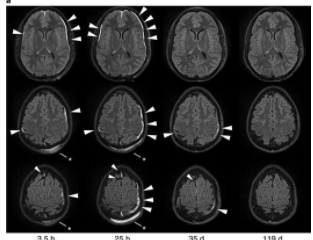

In the study, titled Distinct Myeloid Cell Subsets Promote Meningeal Remodeling and Vascular Repair After Mild Traumatic Brain Injury, published in the journal of Nature Immunology, the authors documented vascular damage in patients who suffered traumatic brain injury. They noted that following injury a ‘clean up crew’ entered the area of injury and cleaned up dead cells. From there a ‘repair crew’ entered which repaired the damages blood vessels.

Of note, if a second mild traumatic brain injury occurred during ‘clean up’ phase the repair phase failed to take place. In an interview discussing these findings to MedicalExpress.com Dr. McGavern noted “Following a head injury, the meninges call in a clean-up crew, followed by a separate repair crew, to help fix damaged blood vessels…The timing of a second head injury may determine whether the meninges can be repaired. We have shown on a cellular level, that two or more head injuries within a very short amount of time can have really dire consequences for the brain lining and its ability to repair…It is possible that patients who did not fully recover following a head injury may have had problems with the first phase of the repair process“.